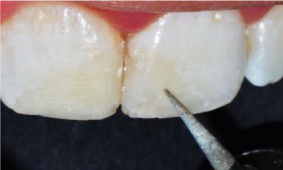

Clinical examination (figure 1a) revealed defective resin composite restoration on teeth #21 and #11. Tooth#21 showed an access cavity already done, with a clear discoloration. Sensitivity tests showed positive response only on tooth #11. The tooth #21 was tender to percussion with a physiological mobility. The periodontal state was unhealthy. The gingiva was inflamed with plaque and calculus on teeth. Periapical radiographic examination (figure 1b) showed an immature open apex of the tooth #21 with a radiolucent lesion in the apical area.

Figure 1a. Initial clinical view of the anterior maxillary region: observe the defective restorations of teeth 11 and 21 with discoloration on tooth 21.